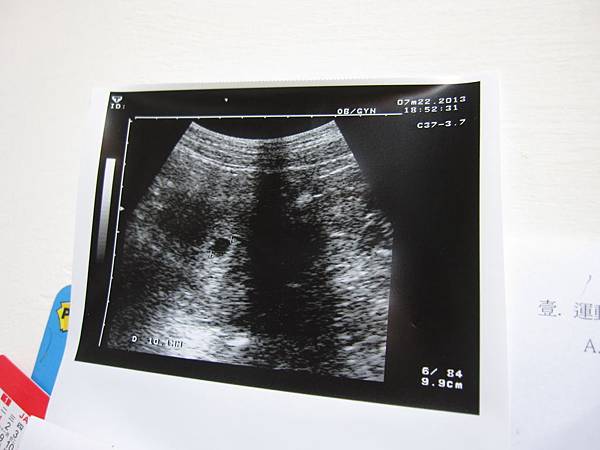

當天晚上便去臺安醫院照了一下超音波

醫生說,因為還只是個胚胎,所以過兩周後再來照

診斷目前懷孕周數約七周又三天

目前胚胎約8mm,已經有心跳了

不過她說我子宮上方有血,要注意